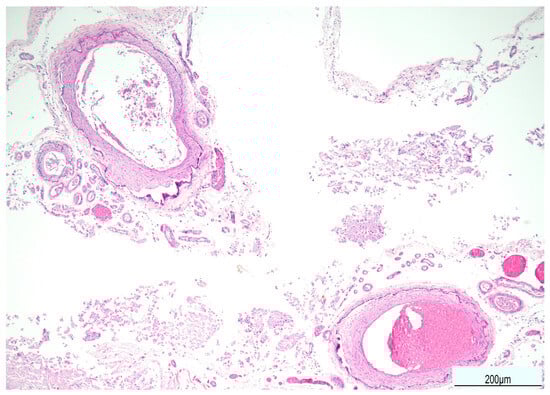

Tissue samples were formalin-fixed, paraffin-embedded, and stained with hematoxylin–eosin. Brain samples were very soft and most of the sections were disrupted after tissue processing. The brainstem showed neuronal ischemic changes, while the cerebellum showed ischemic features with Purkinje cell loss. The brain documented diffuse cortical and subcortical leukomalacia with neuronal loss, isomorphic and anisomorphic gliosis with reactive astrocytes and gemistocytes, Rosenthal fibers, and ferruginated residual neurons (Figure 4 and Figure 5). The meningeal arteries presented sub-adventitial mineralization of the tunica media and calcification of the external elastic lamina (Figure 6). Scattered microcalcifications were also found in the cerebral parenchyma as well as mineralization of the small and medium vessels. Special stains were not carried out as the histological findings were sufficiently informative for interpretation.

Figure 4. Right brain cortex: cystic leukomalacia was prominent with cortical atrophy and disrupted white matter. The blue arrow indicates a meningeal vessel showing sub-adventitial calcification (Hematoxylin and Eosin, 2 HPF).